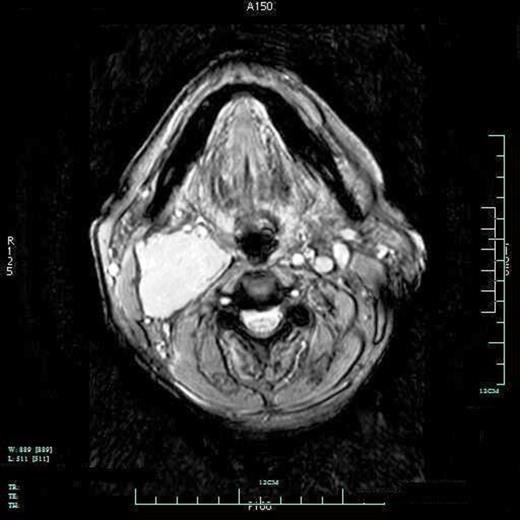

CT angiogram (Figure 1) confirmed the palpable neck mass to be a glomus vagale. A 4cm x 4cm x 8.5cm vascular lesion was found posterior to the carotid sheath with anterior displacement of carotid bifurcation and the internal carotid artery. The vascular lesion extended from the level of the proximal carotid bifurcation to the skull base. There was no evidence of superior extension. The right jugular bulb remained intact and hypoplastic when compared to the left jugular bulb. There was evidence of effacement of the oropharynx by the mass. Inner ear structures were clear and brain parenchyma and ventricles were unremarkable. Lung apices and bone were also unremarkable for metastases. No contralateral cervical lesions were present. CT scan of the abdomen and pelvis was unremarkable. No adrenal or retroperitoneal masses or enlarged lymph nodes were identified. Results confirmed the lack of a coincidental pheochromocytoma.

CT angiography of a 4 x 4 x 8.5cm right glomus vagale. Mass is located posterior to the carotid sheath with anterior displacement of carotid bifurcation and the internal carotid artery.